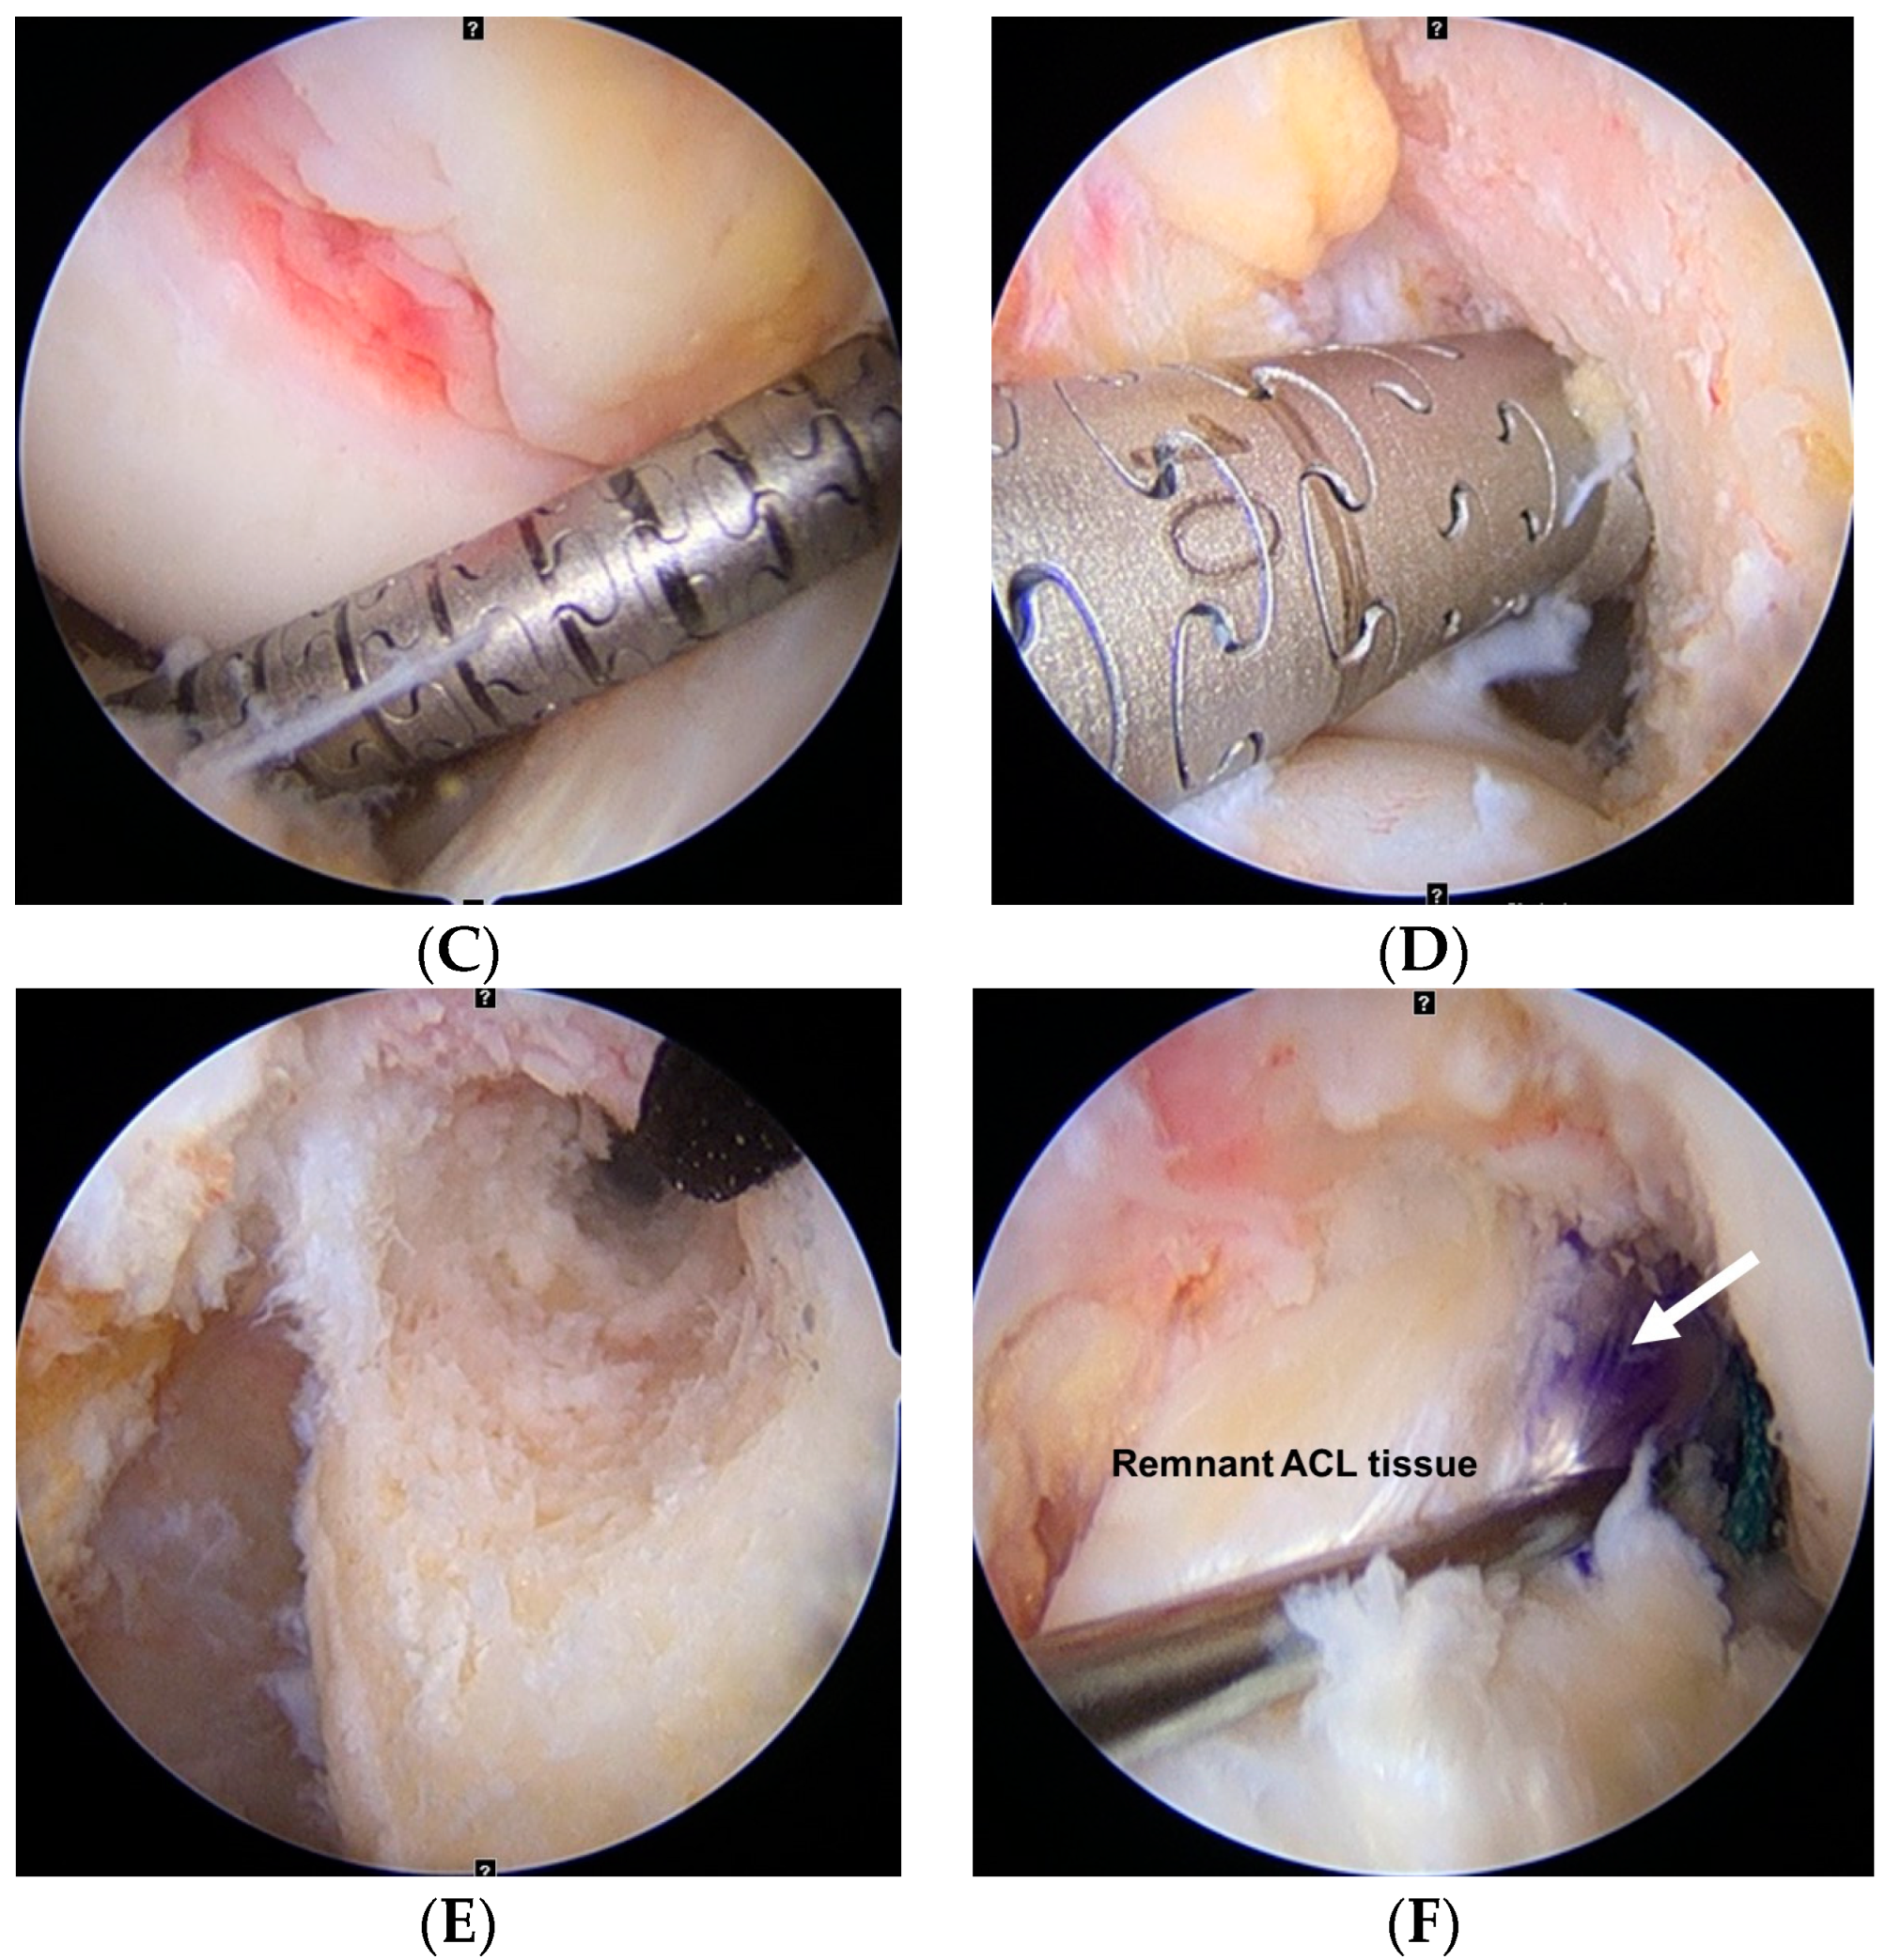

The ACL femoral attachment was removed to identify the bony landmarks (lateral intercondylar ridge and bifurcate ridge) while preserving the remnant tissue substantially using electrocautery (ArthroCare, Smith & Nephew; Austin, TX, USA). While visualizing through the AL portal, the center of the femoral tunnel was marked inferior to the lateral intercondylar ridge and just behind the bifurcate ridge using a microfracture awl through the AAM portal, with the knee in 90° of flexion (Figure 1A). The tunnel center was determined using an arthroscopic bendable ruler (Smith & Nephew Endoscopy, Andover, MA, USA), ensuring that the posterior wall remained 2–3 mm. A 45° curved drill guide was introduced through the AAM portal to the center of the femoral tunnel with superolateral trajectory viewing through the AL portal. A flexible guide pin was inserted through the curved drill guide and drilled with the knee in 100° of flexion (Figure 1B). After the curved drill guide was removed, a flexible reamer of 4.5 mm diameter was drilled out through the far cortex to pass through a suspensory fixation device (Figure 1C). A flexible reamer of a diameter equal to that of the prepared graft was drilled at the same knee flexion angles (Figure 1D). The femoral tunnel was confirmed via the AM portal (Figure 1E). An ACL guide (Linvatec; Largo, FL, USA) was used to establish the tibial tunnel at an angle of 47.5°. The ACL guide tip was located just anteromedial to the center of the ACL bundles. A rigid reamer of a diameter equal to that of the prepared graft was drilled to protect the remnant ACL bundles. The prepared graft was passed from the tibial tunnel to the femoral tunnel. If the femoral tunnel length was 35 mm or longer, EndoButton (Smith & Nephew; Andover, MA, USA) with 15 mm tape was used for fixing. In contrast, if it was shorter than 35 mm, UltraButton (Smith & Nephew; Andover, MA, USA) was used for femoral fixation to maintain the 20 mm or longer graft length within the tunnel. The tibial side was dually fixed using a bioabsorbable interference screw (Matryx, ConMed Linvatec; Largo, FL, USA) and an additional cortical screw or staple with the knee in 20° of flexion. The diameter of the interference screw was equal to that of the tibial tunnel. Finally, the reconstructed ACL graft containing the original remnant ACL tissue was evaluated (Figure 1F).

Figure 1.

Anterior cruciate ligament (ACL) reconstruction of the left knee. (A) Anatomic center of the femoral tunnel is marked inferior to the lateral intercondylar ridge and just behind the bifurcate ridge (dotted line) using a microfracture awl through the accessory anteromedial (AM) portal, with the knee in 90° of flexion. (B) A flexible guide pin is inserted and drilled with the knee in 100° of flexion. (C) A flexible reamer of 4.5 mm diameter is drilled out through the far cortex to pass through a suspensory fixation device. (D) A flexible reamer of a diameter equal to that of the prepared graft is drilled. (E) The femoral tunnel is confirmed via the AM portal. (F) After tibial fixation, the reconstructed ACL graft containing the remnant tissue is evaluated.